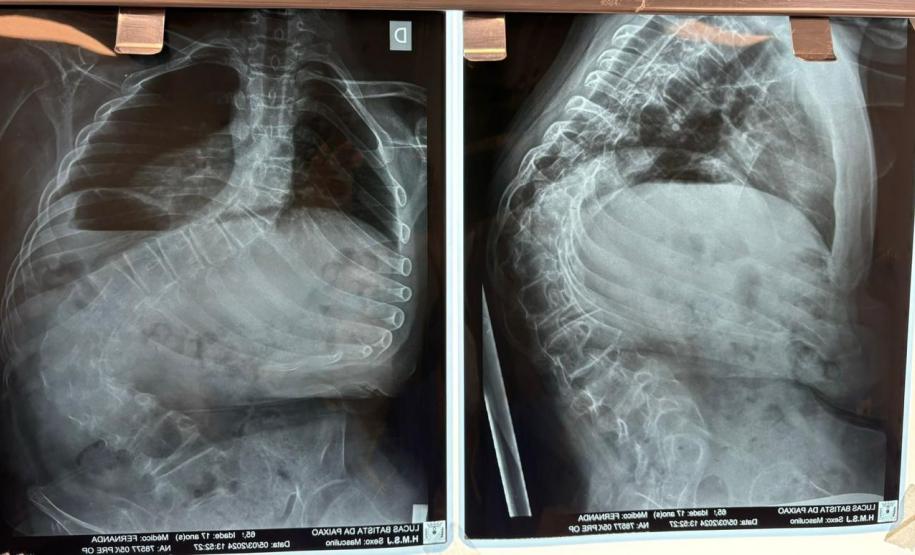

Outro tipo de escoliose é a causada por doenças neuromusculares, como paralisia cerebral, mielomeningocele, distrofia muscular, atrofia muscular espinhal, entre outras. No caso do Lucas Batista da Paixão, de 18 anos, a paralisia cerebral que teve ao nascer foi o que desencadeou a condição.

Com curvatura acima dos 100 graus, desconfortos respiratórios como falta de ar e asma, a posição do adolescente na cadeira de rodas estava bem limitada. Para a mãe de Lucas, Daniele de Oliveira Batista, a cirurgia foi fundamental para melhorar a autonomia e qualidade de vida do filho.